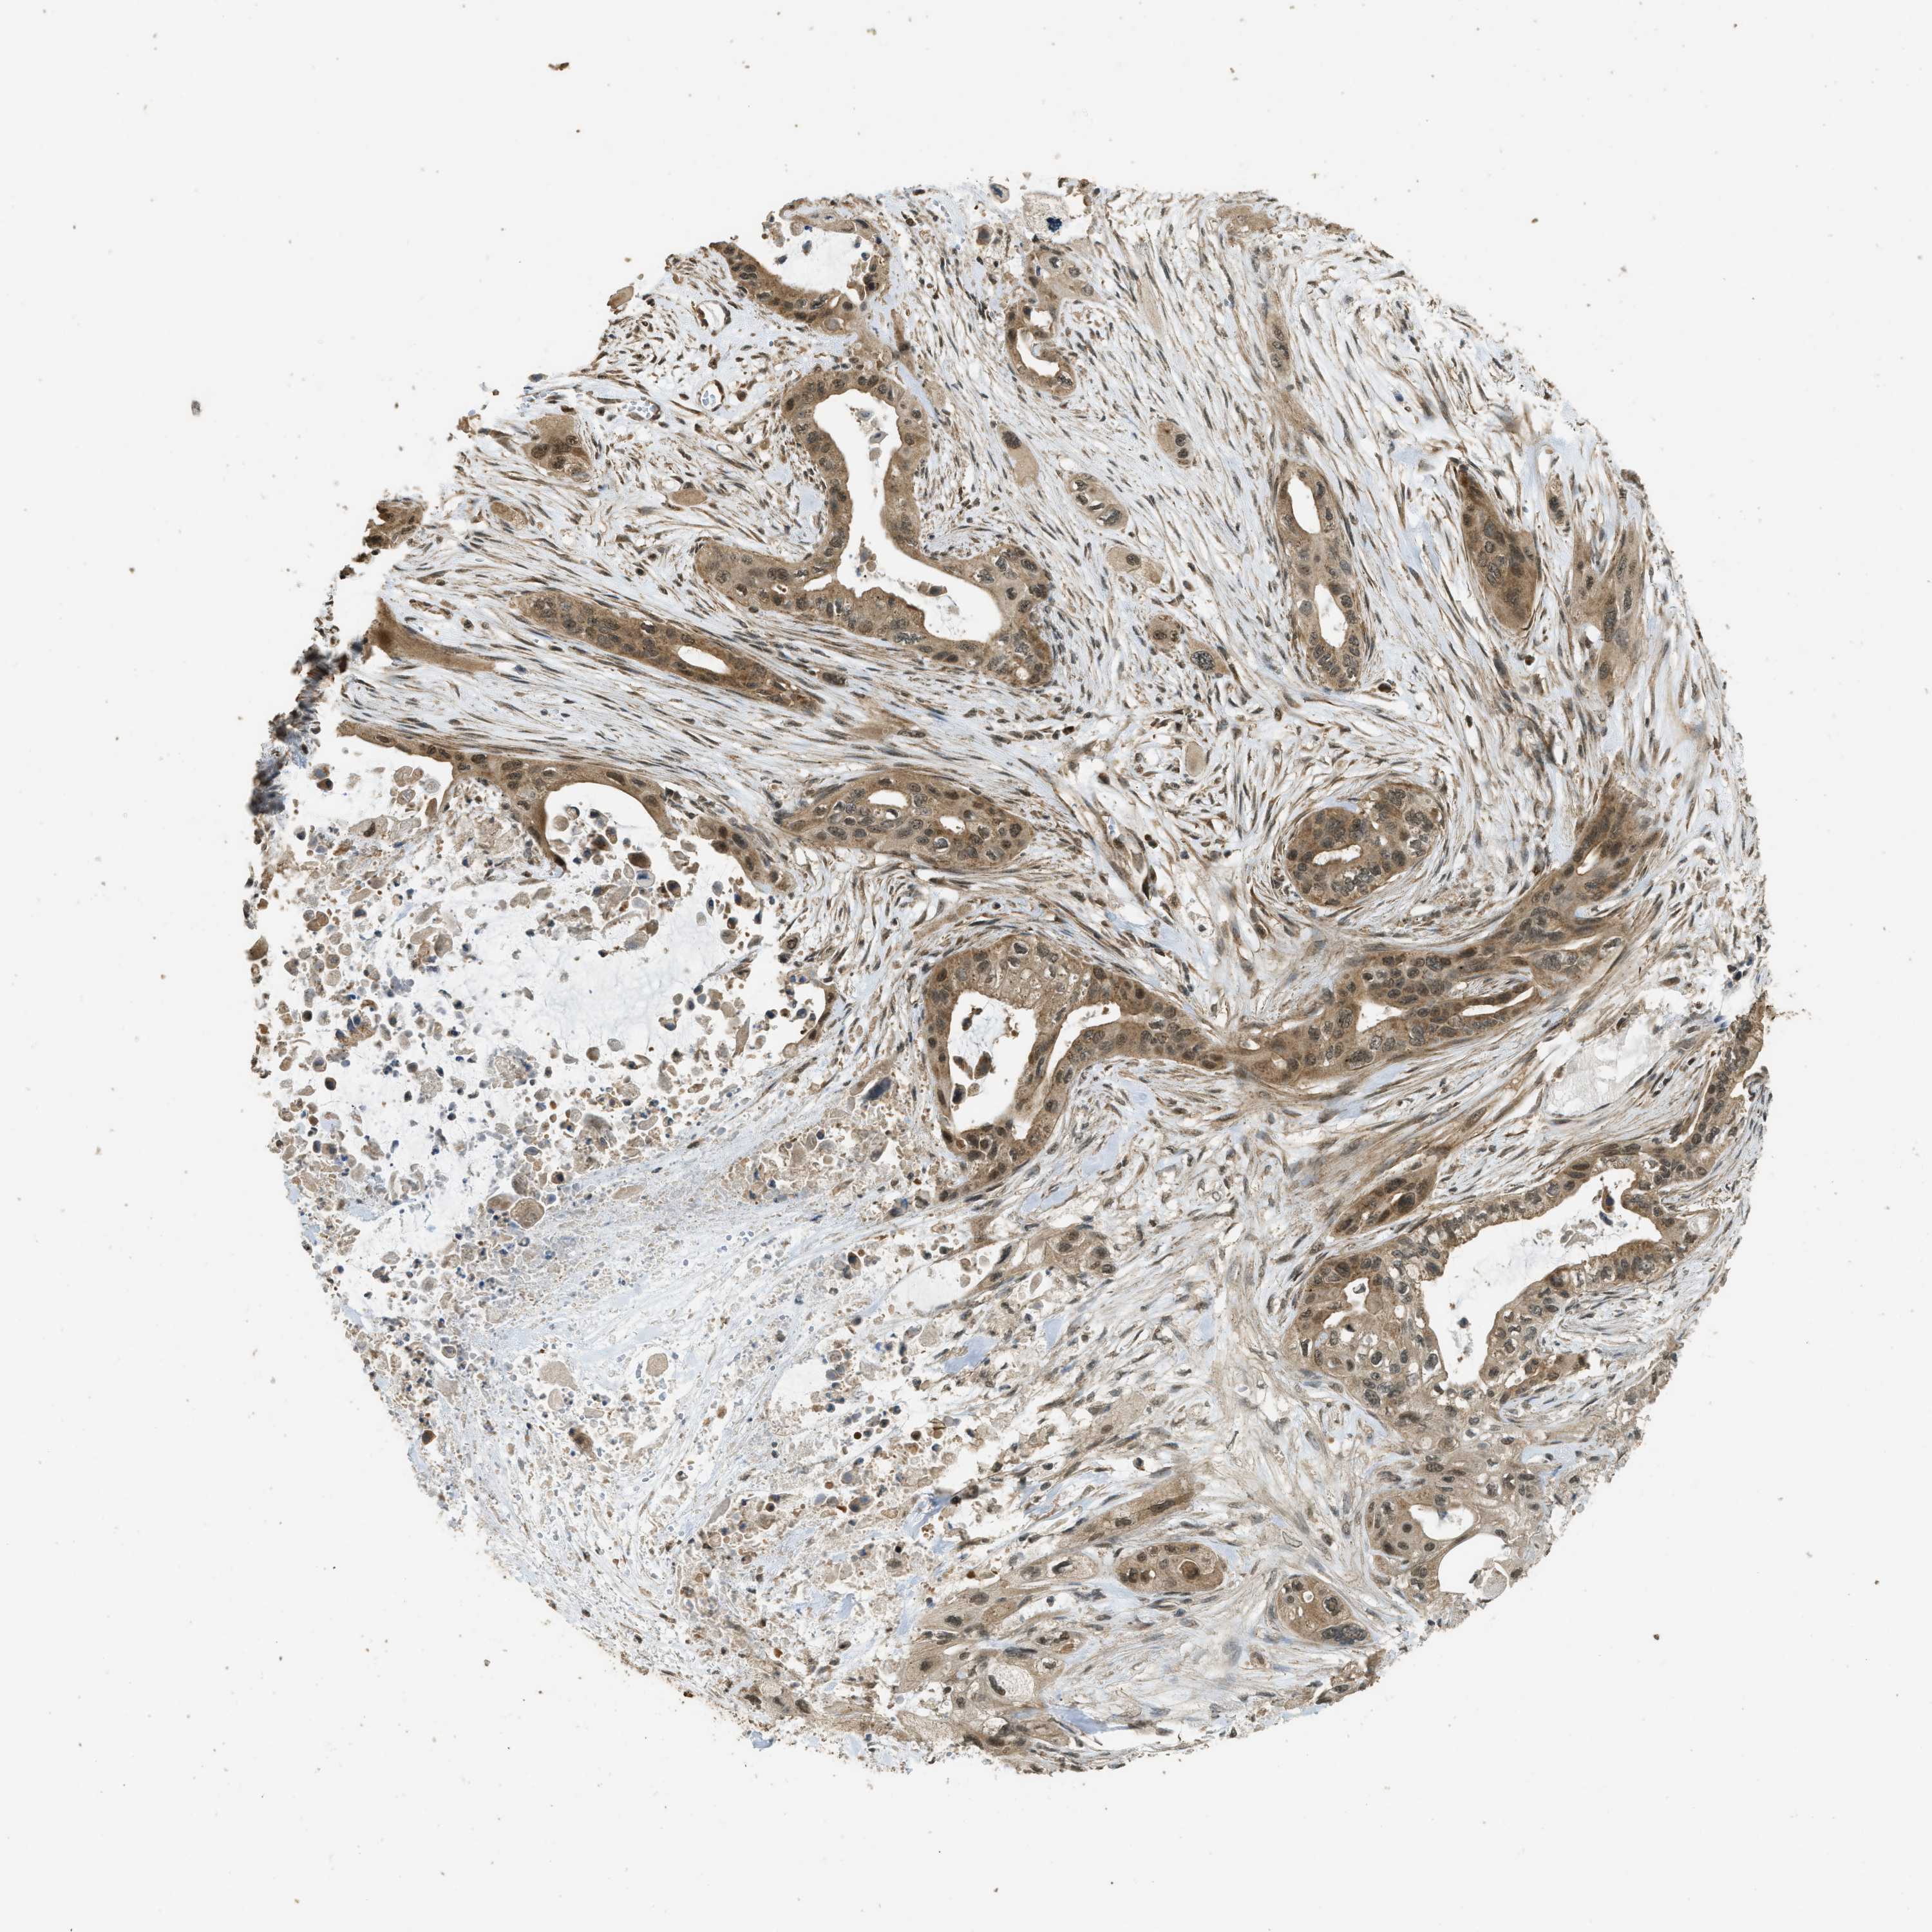

PANCREATIC CANCER - Protein expressioni

A mouse-over function shows sample information and annotation data. Click on an image to view it in a full screen mode. Samples can be filtered based on level of antibody staining by selecting one or several of the following categories: high, medium, low and not detected. The assay and annotation is described here.

Note that samples used for immunohistochemistry by the Human Protein Atlas do not correspond to samples in the TCGA dataset.

Antibody stainingi

Antibody staining in the annotated cell types in the current human tissue is reported as not detected, low, medium, or high, based on conventional immunohistochemistry profiling in selected tissues. This score is based on the combination of the staining intensity and fraction of stained cells.

Each image is clickable and will lead to virtual microscopy that enables deeper exploration of all samples and also displays staining intensity scores, fraction scores and subcellular localization as well as patient and tissue information for each sample.

Antibody HPA051322

Antibody CAB017111

Staining

High

Medium

Low

Not detected

Intensity

Strong

Moderate

Weak

Negative

Quantity

>75%

75%-25%

<25%

None

Location

Nuclear

Cytoplasmic/membranous

Cytoplasmic/membranous,nuclear

Adenocarcinoma, NOS